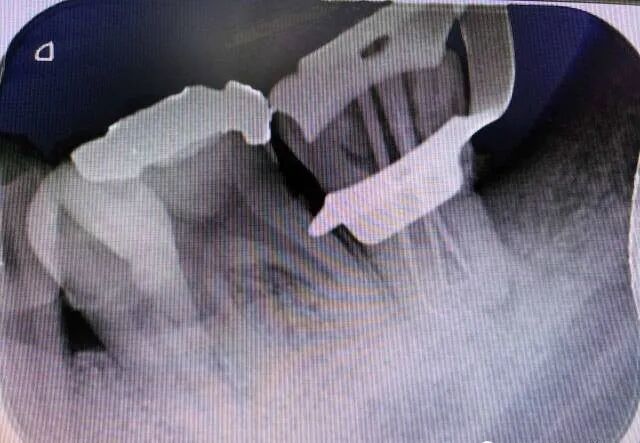

定位根管口:结合CBCT,显微镜的照明和放大功能来准确定位根管口;采用超声设备去除根管上段钙化物,同时,配合使用小号 C 锉和以及 EDTA 根管凝胶疏通根管;分别沿着不同根管口的方向插针拍摄X线片以进行核对。 -

图10 47根充片